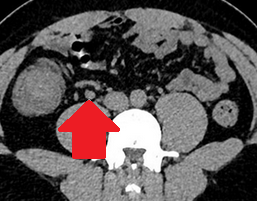

Σχήμα 1 . Η αξονική τομογραφία με ενισχυμένη με σκιαγραφικό έδειξε μια ακανόνιστη περιφερική μάζα στο αριστερό μισό του εγκάρσιου κόλου με λιπώδη συσσωμάτωση δίπλα σε παχυσμένο τοίχωμα του εντέρου. ( Ευγενική παραχώρηση Δρ. Β. Πενόπουλος ) .